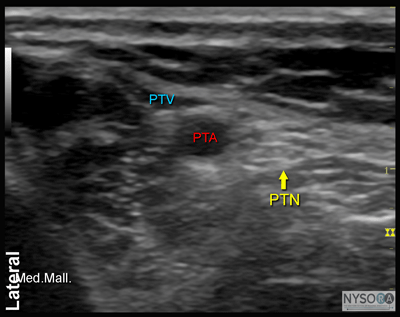

![]() Figure 2: Cross-sectional anatomy of the posterior tibial nerve at the level of the ankle. Shown are posterior tibial artery (PTA) and vein (PTV) behind the medial malleolus (Med. Mall.) The posterior tibial nerve (PTN) is just posterior and superficial to the posterior tibial vessels. General Considerations Using an ultrasound-guided technique affords a practitioner the ability to reduce the volume of local anesthetic required for ankle blockade. Because the nerves involved are located relatively close to the surface, ankle blocks are easy to perform technically; however, knowledge of the anatomy of the ankle is essential to ensure success. Ultrasound Anatomy Ankle block involves anesthetizing five separate nerves: 2 deep nerves and 3 superficial nerves. The 2 deep nerves are tibial (TN) and deep peroneal nerve (DPN). The superficial nerves are superficial peroneal, sural and saphenous. All nerves except saphenous nerve are terminal branches of the sciatic nerve; saphenous nerve is a cutaneous extension of the femoral nerve. Tibial Nerve The tibial nerve is the largest of the five nerves at the ankle level and provides innervation to the heel and sole of the foot. With a linear transducer placed transversely at (or just proximal to) the level of the medial malleolus, the nerve can be seen immediately posterior to the posterior tibial artery (Figures 1, 2, and 3A and B). Color Doppler can be very useful in depicting the posterior tibial artery when it is not readily apparent. The nerve typically appears hyperechoic with dark stippling. A useful mnemonic for the relevant structures in the vicinity is Tom, Dick ANd Harry, which refers to, from anterior to posterior, the tibialis anterior tendon, flexor digitorum longus tendon, artery/nerve/ vein, and flexor hallucis longus tendon. These tendons can resemble the nerve in appearance, which can be confusing. The nerve's intimate relationship with the artery should be kept in mind to avoid misidentification.

Figure 3: (A) Ultrasound image of the posterior tibial nerve. (B) Posterior tibial nerve (PTN) is seen posterior to the posterior tibial artery (PTA). Med. Mall., medial malleolus; PTV, posterior tibial vein. Deep Peroneal Nerve This branch of the common peroneal nerve innervates the web space between the first and second toes. As it approaches the ankle, the nerve crosses the anterior tibial artery from a medial to lateral position. A transducer placed in the transverse orientation at the level of the extensor retinaculum will show the nerve lying immediately lateral to the artery, on the surface of the tibia (Figures 4, 5, and 6A, B). The nerve usually appears hyperechoic, but it is small and often difficult to distinguish from the surrounding tissue.